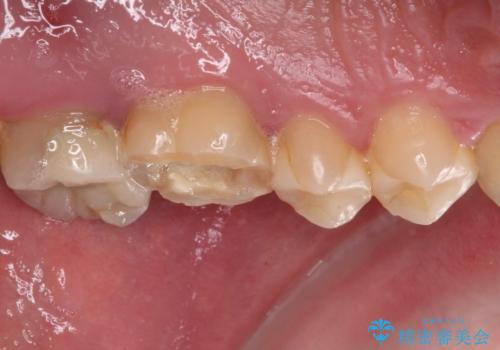

- 近医にて、虫歯が大きいため抜歯が必要と言われたとのことで来院された患者様です。

診査したところ、根尖部の病変は大きいものの、抜歯が必要とは決して思えず、まずは根管治療を行うべきと判断しました。